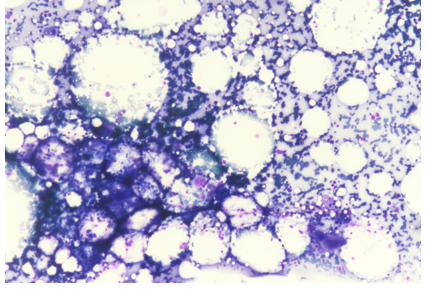

The patient's medical history, clinical presentation, and laboratory findings raised concerns about bone marrow suppression. Further investigations were performed to identify the cause. Peripheral blood smear examination revealed normocytic normochromic red blood cells with reduced platelet count and decreased leukocyte population. Bone marrow aspiration and biopsy were performed to evaluate the bone marrow function and morphology. The bone marrow examination showed “Maturation Arrest” with normo to hypercellular cellular marrow with decreased cellularity and reduced myeloid-to-erythroid ratio Ret count 0.6. There was no evidence of infiltrative or neoplastic processes.

Figure 1: Mega 10x

Figure 2: Trephine Biopsy